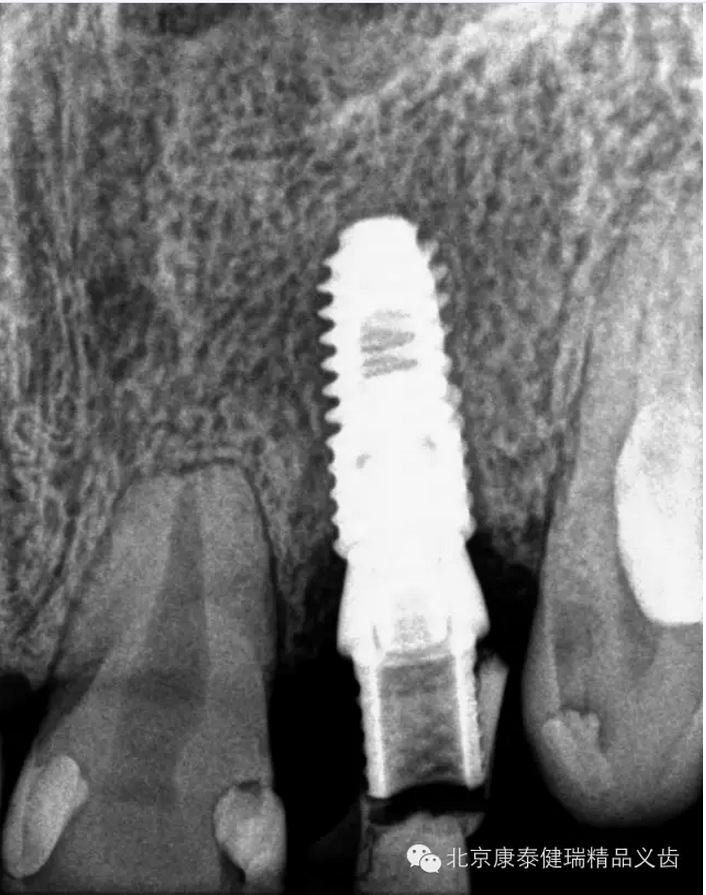

【口腔種植】數(shù)字化種植案例展示